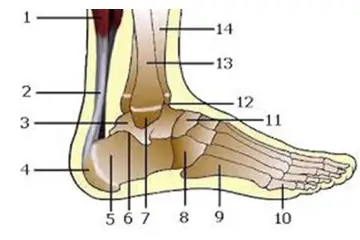

- Görüntüleme yöntemleri: Röntgen, MRI (Manyetik Rezonans Görüntüleme) ve CT (Bilgisayarlı Tomografi) gibi yöntemler, kemik yapısını değerlendirmek için kullanılır.